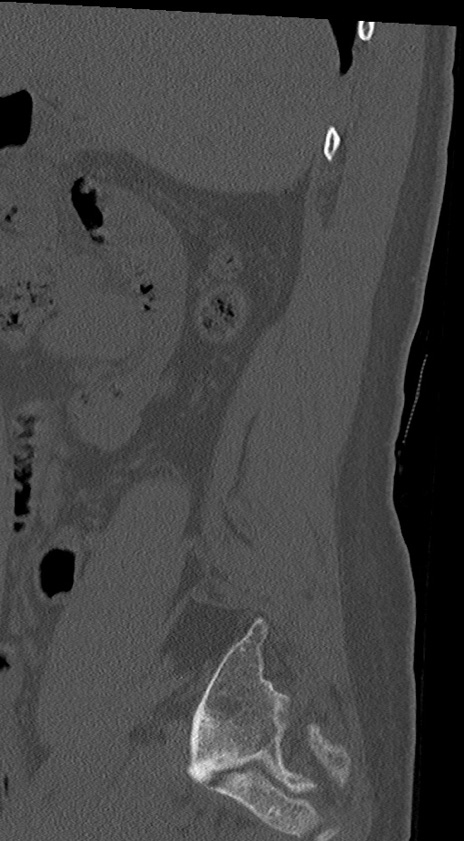

【整形】TIPS症例4 腰椎CT(矢状断像)

腰椎CT

冠状断像